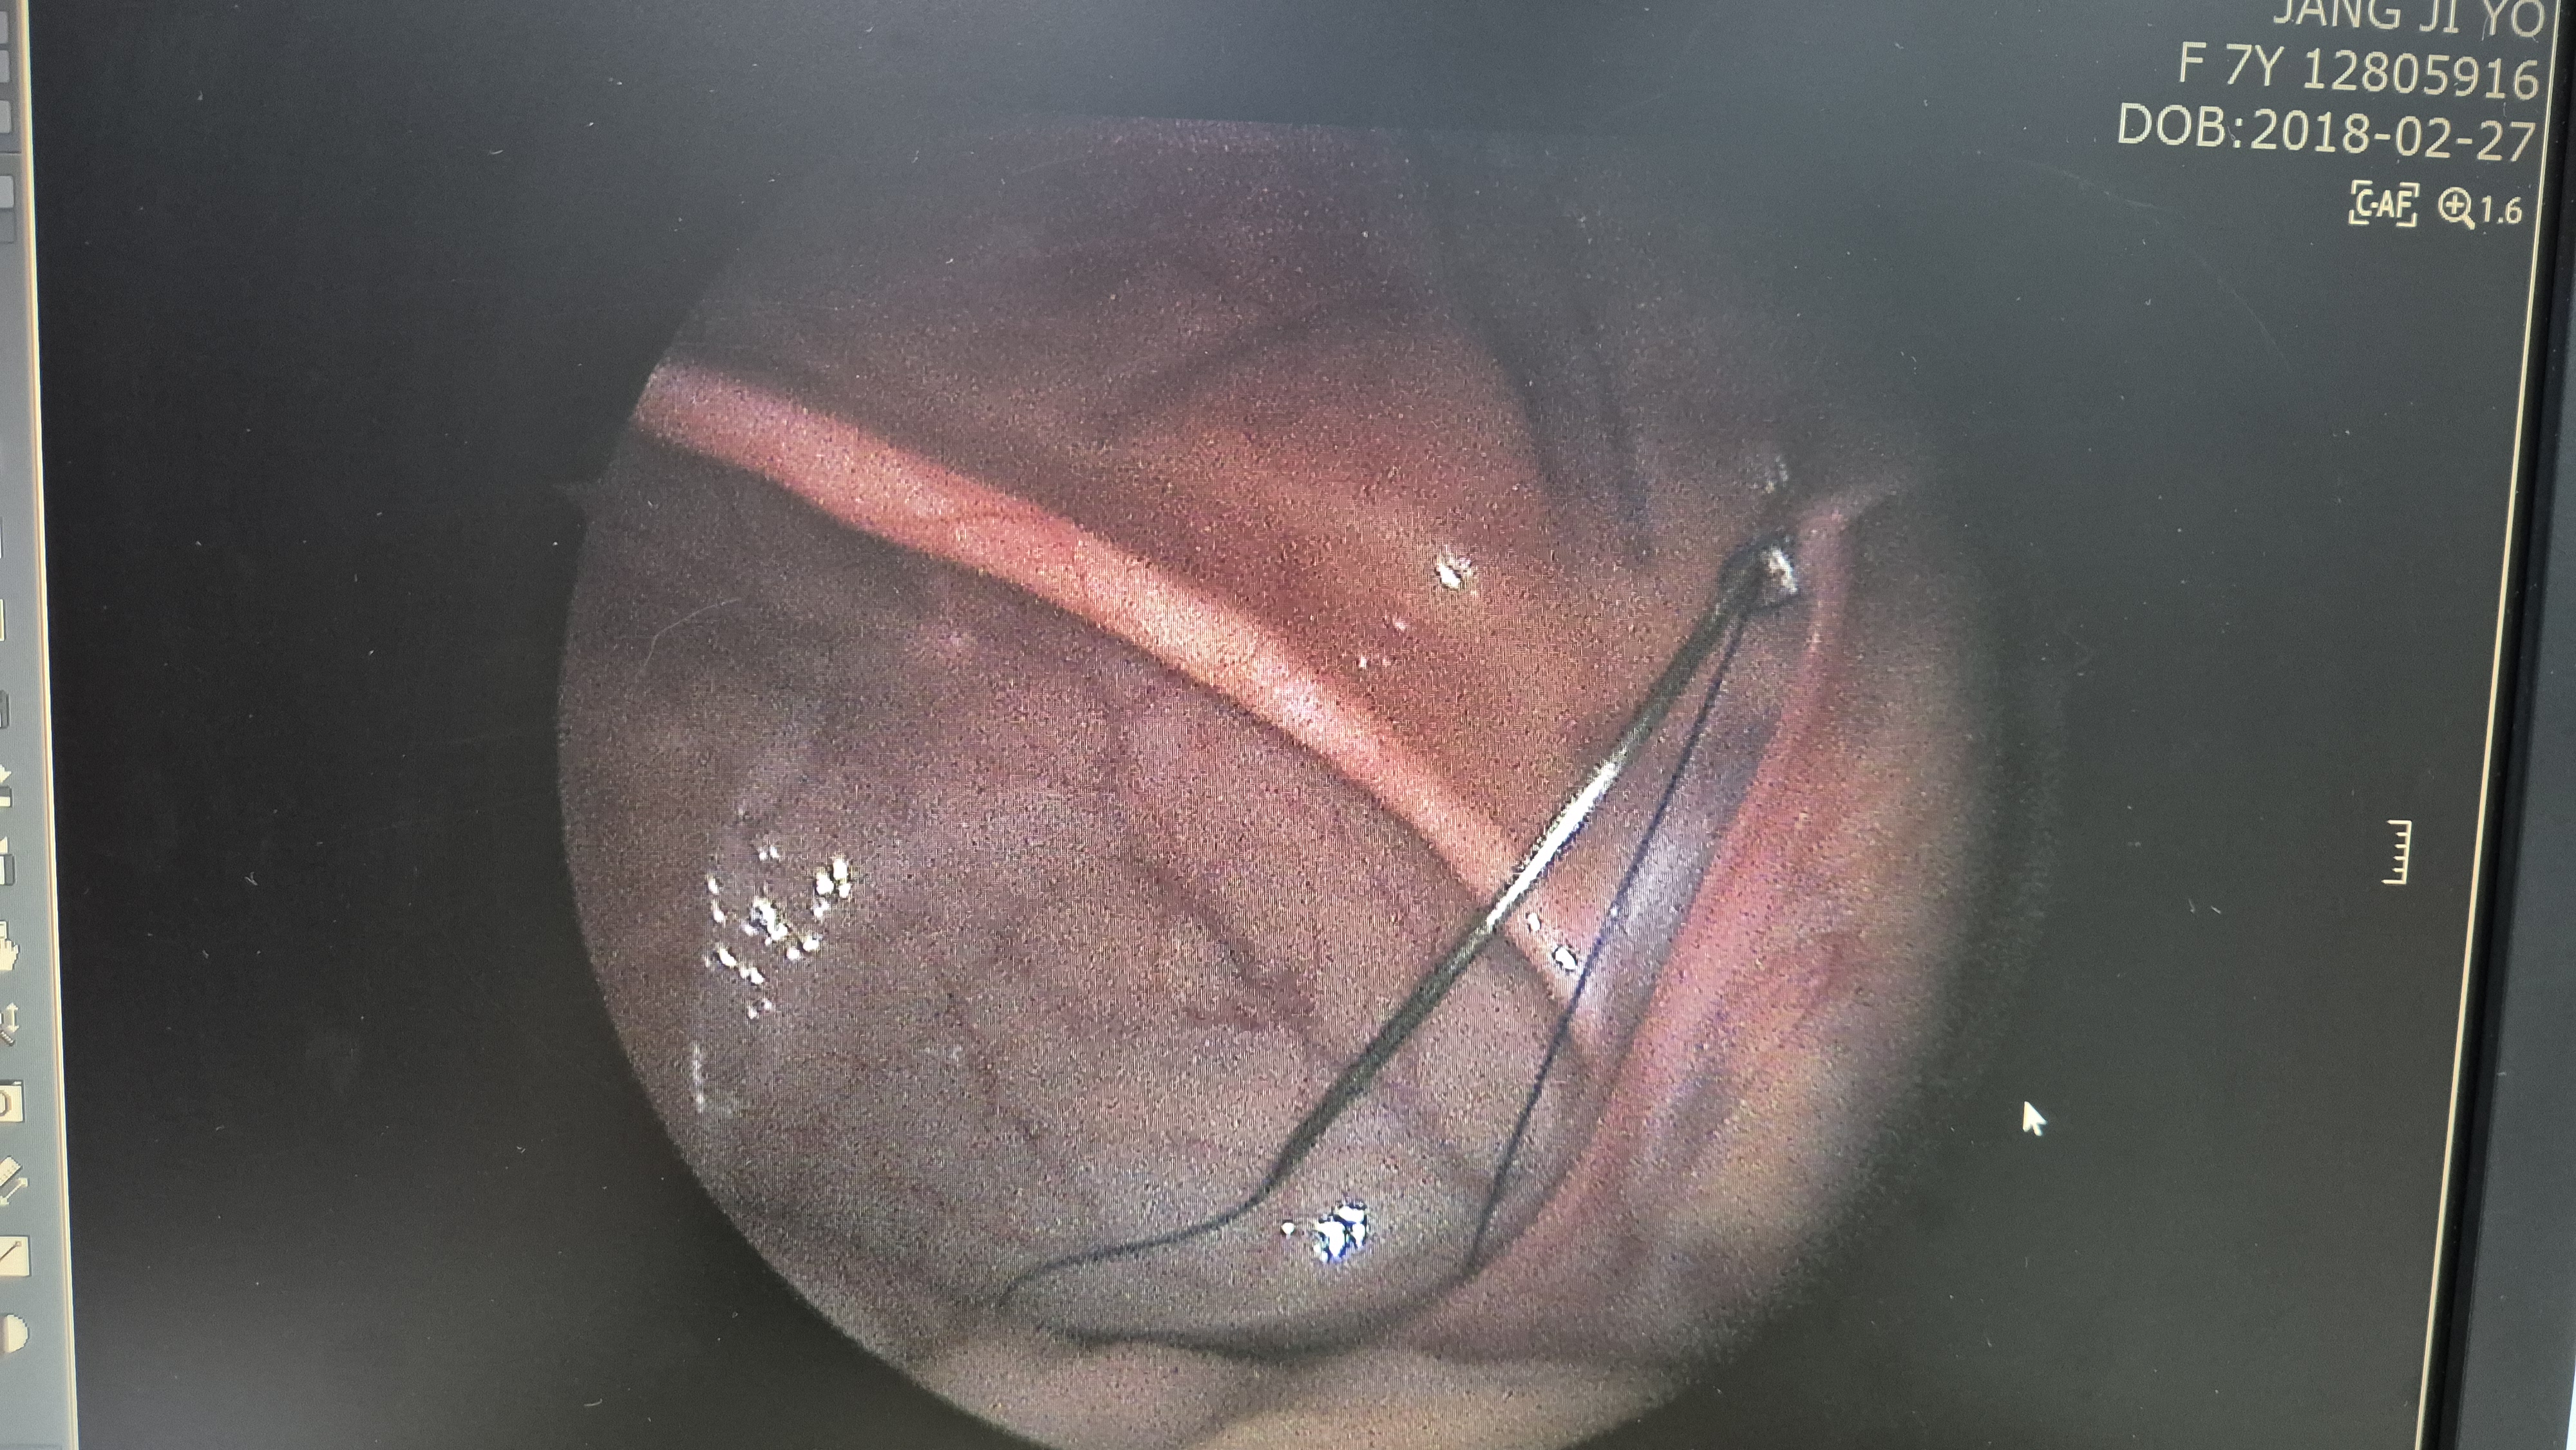

우측 서혜부 탈장.

교정중.